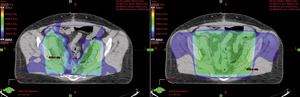

Teleradioterapia, napromienianie wiązkami zewnętrznymi, jest prowadzona głównie przy użyciu wysokoenergetycznych fotonów X, generowanych w przyspieszaczach liniowych. W wybranych sytuacjach mają też zastosowanie wiązki elektronów o różnie dobieranych energiach. Coraz rzadziej stosowane jest promieniowanie gamma kobaltu 60. Postęp technologiczny i dostępność komputerowych systemów planowania przestrzennego radioterapii, opartych na nowoczesnych technikach obrazowania, umożliwiły w większości ośrodków planowanie radioterapii dostosowawczej (konformalnej), realizowanej według indywidualnie przygotowanych planów leczenia. Planowanie pól napromieniania odbywa się przestrzennie – trójwymiarowo (3D), z wykorzystaniem przekrojów tomografii komputerowej, na których lekarz oznacza guz nowotworowy, elektywny obszar do napromienienia (regionalne węzły chłonne z adekwatnym marginesem) i narządy krytyczne (ryc. 1). W wybranych przypadkach w planowaniu wykorzystuje się połączenia obrazów z badaniem pozytonową tomografią emisyjną (PET-TK), co daje możliwość zwiększenia dawki w obszarze dużej aktywności metabolicznej guza nowotworowego lub jego przerzutów do regionalnych węzłów chłonnych (ryc. 2).1,2 Za pomocą komputerowych systemów planowania leczenia fizyk tworzy indywidualny plan leczenia, który powinien spełniać kryteria jednorodnego rozkładu dawki promieniowania w planowanej objętości napromienianej (PTV) oraz dużego gradientu dawki poza tą objętością. Jednocześnie nie należy przekraczać ustalonych dawek tolerancji w narządach krytycznych (OR) (ryc. 3). Dopasowanie kształtu pola napromieniania do konturu planowanej objętości napromienianej osiąga się, stosując kolimatory wielolistkowe o zmiennym kształcie. Poprawność planowania radioterapii oparta na kryteriach zebranych w raportach 50 i 62 International Commission on Radiation Units (ICRU) dokumentują histogramy rozkładu dawki promieniowania w planowanej objętości i w wybranych narządach krytycznych (ryc. 4). Ośrodki wyposażone w nowoczesne wysokoenergetyczne przyspieszacze liniowe i wysoko wydajne systemy planowania radioterapii mogą stosować radioterapię z użyciem modulacji intensywności dawki promieniowania (intensity modulated radiation therapy, IMRT). Główną zaletą tej techniki jest możliwość modelowania dawki całkowitej promieniowania w obszarze napromienianym z oszczędzeniem struktur krytycznych (ryc. 5).3 Technika dwuwymiarowa (2D) stosowana jest nadal z powodzeniem w przypadkach leczenia paliatywnego. Stosuje się wówczas najprostsze techniki dwu pól przeciwległych i czteropolową technikę „box”, polegającą na napromienianiu odpowiednio na dwa lub cztery pola wlotowe, których płaszczyzny są parami równolegle. Powyższe napromienianie nie gwarantuje jednak jednorodnego rozkładu dawki promieniowania w wyznaczonej objętości. Stwarza ono też ryzyko przedawkowania ponad należną dawkę promieniowania w obrębie narządów krytycznych.